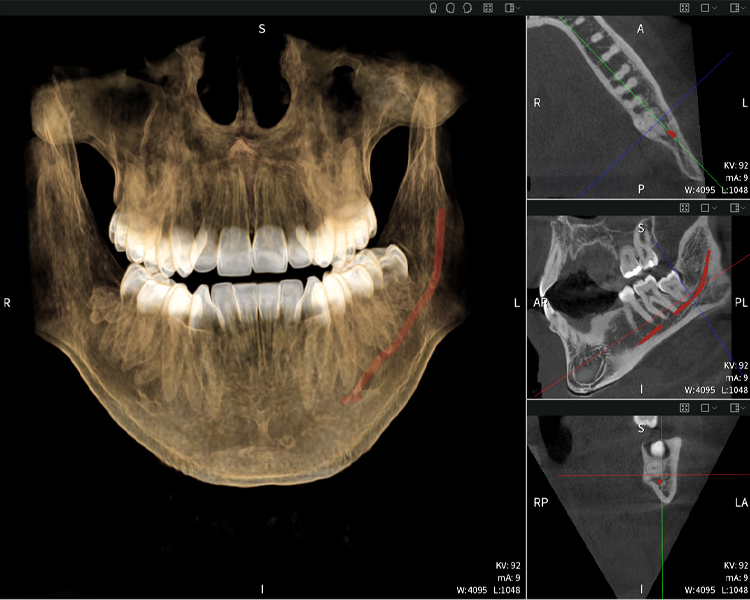

A continuación encontrarás un caso del Dr. med. dent. Oliver A. Centrella, en el cual las imágenes CBCT obtenidas con Seethrough Max proporcionaron información crucial sobre la anatomía compleja y la relación crítica entre las muelas del juicio y el nervio alveolar inferior. En este caso, existe una indicación para la extracción quirúrgica de las muelas del juicio.

Figura a: Resultados de imagen de Seethrough Max, sobre un fondo negro.

Figura a

• Arriba a la izquierda: Corte axial de la mandíbula izquierda (región 38) que muestra el nervio alveolar inferior (en rojo) en proximidad a las raíces del diente 38.

• Arriba a la derecha: Reconstrucción 3D de toda la mandíbula para orientación. El nervio alveolar inferior marcado en rojo ilustra su ubicación dentro del hueso mandibular.

• Abajo a la izquierda: Vista sagital de la mandíbula (región 38), destacando la estrecha relación espacial entre las raíces y el conducto del nervio.

• Abajo a la derecha: Vista coronal de la mandíbula (región 38), crucial para evaluar la posición espacial de las raíces en relación con el nervio.